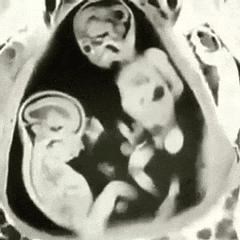

Twins fighting for superiority.